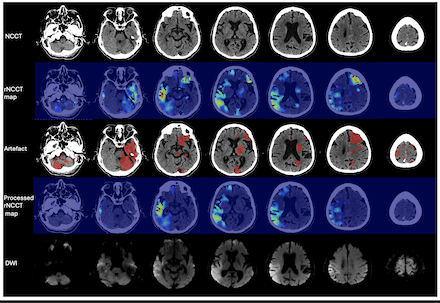

Results: The best performing model was the ensemble of the five cross-validation folds of 3d low- and high-resolution models based on dice similarity coefficient. Figure 1 provides an example of our model’s artefact segmentation and the processed rNCCT map after artefact removal. For the 54 patients (20% of study population) in our test set, our model achieved a median Dice similarity coefficient of 0.95 (IQR: 0.91-0.97) and a median false positive volume of 6.1 (3.2-11) ml. In the 30 patients with available DWI scans, 30% of patients had any overlap (>=1 voxel) between the segmented artefact and DWI ischemic core with a median overlap volume of 0.69 (IQR: 0.32-2.3) ml.